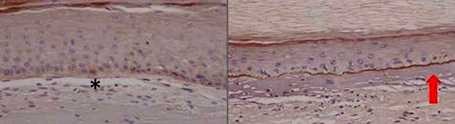

New models of head and neck cancer in Fanconi Anemia patients

New models of head and neck cancer in Fanconi Anemia patients. Fanconi anemia patients are at very high risk of developing squamous cell carcinoma of the head and neck (SCC and C). In...